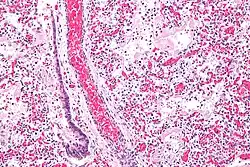

Микрофотография диффузного поражения альвеол при ОРДС. Окраска гематоксилином и эозином.

В основе ОРДС лежит диффузное воспаление лёгких. В этом процессе выделяют 3 фазы: экссудативная, пролиферативная и фибротическая[8].

В экссудативную фазу в ответ на воспаление выделяются цитокины и другие провоспалительные вещества, которые активируют альвеолярные макрофаги и циркулирующие нейтрофилы. В свою очередь, активированные нейтрофилы прикрепляются к эндотелию лёгочных капилляров и высвобождают содержимое своих цитоплазматических гранул (протеазы и токсические метаболиты кислорода)[10]. Это приводит к повреждению эндотелия капилляров и эпителия альвеол, нарушая альвеолярно-капиллярный барьер. В результате экссудат проникает в лёгочную паренхиму и альвеолярное воздушное пространство. Нарушается газообмен и возникает гипоксия[11]. Также возможно повреждение альвеолоцитов II типа, которые отвечают за образование сурфактанта. При этом происходит спадение альвеол, снижение растяжимости лёгких и внутрилёгочное шунтирование. Кроме того, развивается лёгочная гипертензия в результате внутрисосудистой обструкции тромбами, спазма лёгочных сосудов из-за гипоксии и действия некоторых воспалительных медиаторов (тромбоксан, лейкотриены и эндотелин)[12].